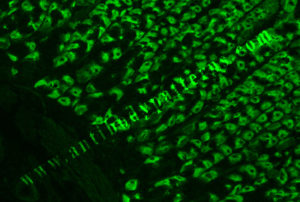

This antibody reacts with H+K+-ATPase in the parietal cells.

Image: Rodents stomach stained with IgG from patient. Note, cell cytoplasm of the gastric parietal cells in green while the nuclei are unstained black. Caution must be exercised as heterophile antibody can also give similar staining distribution.